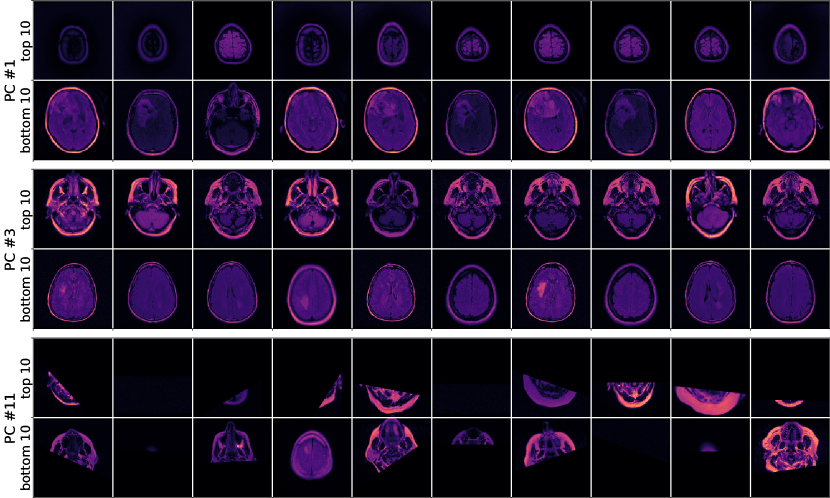

Figure 2: Semantic groups for the MRI (a), CXR (b) and OCT(c) data. Values increase left to right. See the text for an interpretation of the groups.

When ordering the values for each principal component, we discovered that, for most components, the bulk of the datapoints has a value near zero, while only a fraction of samples had high positive or negative values. The curve, which results from ordering the values, resembles a logit function to some extent (see Fig. A.2 in the Appendix). Looking at samples with such extreme values, we saw that these samples, in many cases, shared some semantic structure. In Fig. 2 we demonstrate the semantic grouping that results from our method. Each subfigure shows the results from one of the datasets. For each dataset, we picked three principal components to visualize, showing the ten images with the highest and ten with the lowest value of that principal component. Identifying, which principal component corresponds to which semantic concept is evident in some cases but can be difficult in others. As such, we put the concept we think a component is responsible for in quotation marks. Generally, we find that the difficulty of interpretation increases with the number of the principal component, as was expected given the nature of PCA.

For the MRI data, we picked the principal components for "brain size" (PC #1), "axial position" (PC #3) and "cutoff" (PC #11), as shown in Fig. 2. The "cutoff" component reveals that some images in the dataset are cut off. Interestingly, samples with a high value in this component are cut off at the top, while the ones with low values are cut off at the bottom. Depending on the application, these samples should be inspected more closely and removed from the dataset if need be.